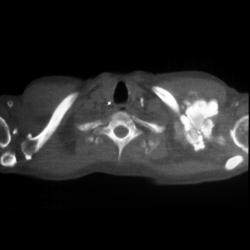

Lymphoma of the Rib